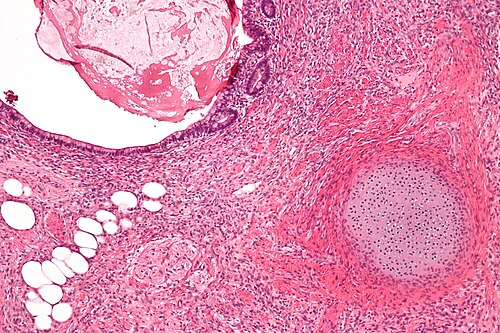

3

Diagnosis?

Teratoma intermed mag.jpg

Adenomatoid tumour

Adenocarcinoma of the rete testis

Adenomatous hyperplasia of the rete testis

Benign testis

Atrophic testis

Choriocarcinoma

Embryonal carcinoma

Immature teratoma

Infarcted testis

Inflamed testis

Intratubular germ cell neoplasia

Leydig cell tumour

Lymphoma

Mature teratoma

Mixed germ cell tumour

Papillary cystadenoma of the epididymis

Seminoma

Spermatocytic seminoma

Sertoli cell tumour

Sertoli cell nodule

Testicular scar

Yolk sac tumour